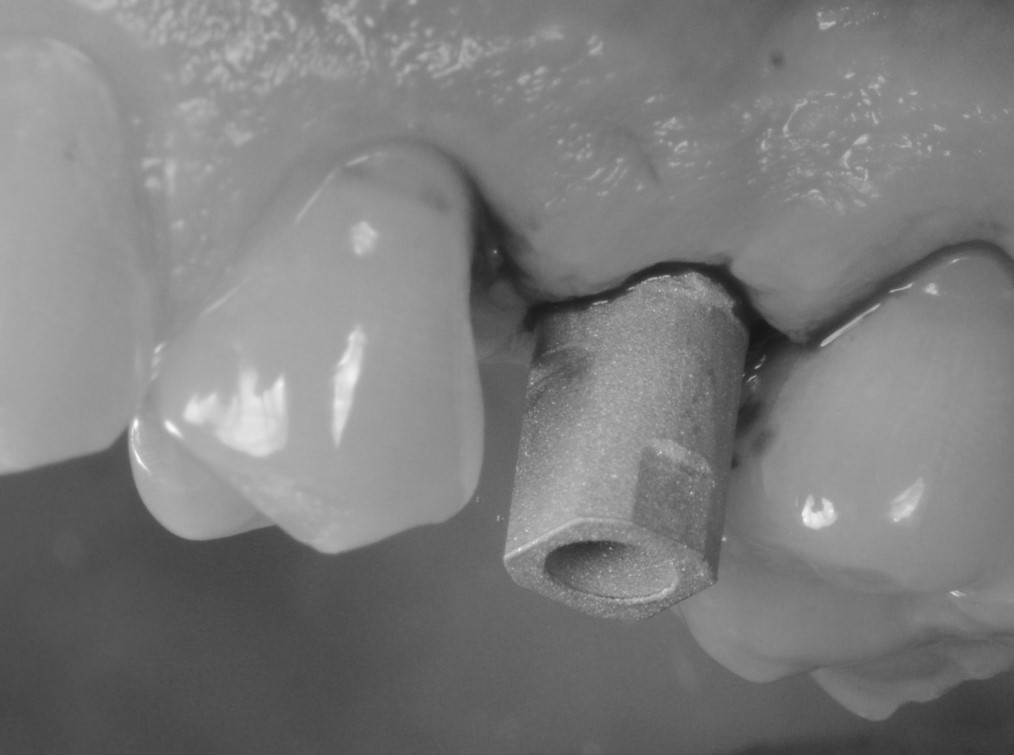

L’impianto prescelto era stampato in 3D (Type K®, AndrewMedical, Carate Brianza, Monza, Italia) con stampante stereolitografica (RenAM 500Q®, Renishaw, Wottonunder-edge, Gloucestershire, UK) e pertanto caratterizzato da una superficie altamente porosa (Fig. 3), in grado di promuovere l’osteointegrazione. Il posizionamento dell’impianto avveniva dopo somministrazione di anestetico locale per infiltrazione, sollevamento di lembo mucoperiosteo a spessore totale, e preparazione del sito con kit implantare dedicato. Inserito l’impianto (Fig. 4), si procedeva a suturare i lembi (Fig. 5).

Visione dell’impianto stampato in 3D

Fig. 3. Visione dell’impianto stampato in 3D (Type K®, AndrewMedical, Carate Brianza, Monza, Italia) prima dell’inserimento.

L’impianto inserito nell’alveolo post-estrattivo

Fig. 4. L’impianto inserito nell’alveolo post-estrattivo.